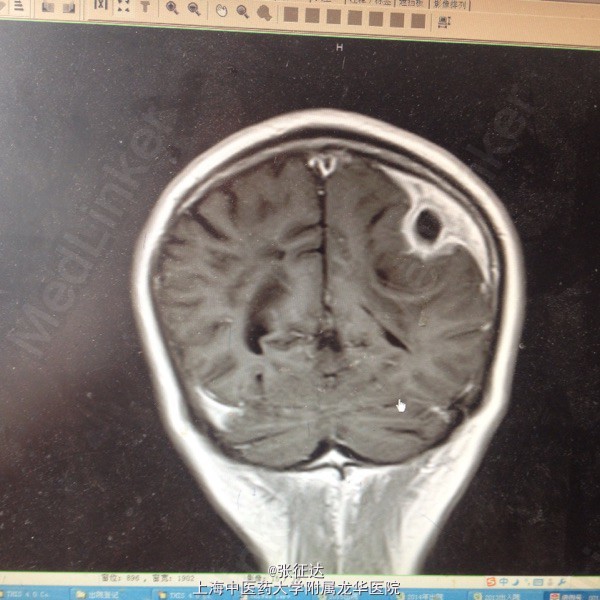

硬膜下血肿术后一月伴右侧肢体活动不利

神情,GCS14分,右侧肢体肌力III级,病理症(-)。头颅CT:左侧顶叶区占位

复查头颅MR表现为左侧顶叶占位。择期全麻下行手术治疗后取病理,提示脑脓肿